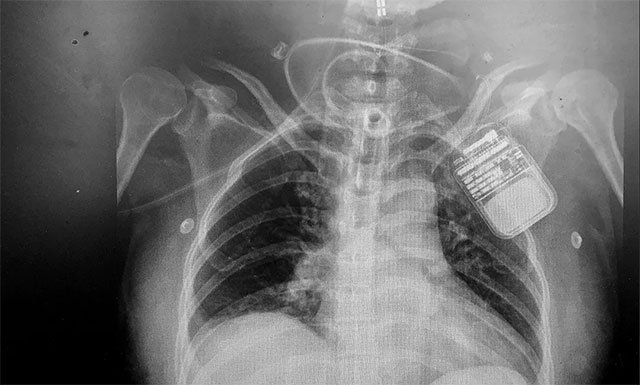

脊髓神經(jīng)電刺激術(shù)是通過微創(chuàng)手術(shù)將電極置入脊髓上方,以脈沖電流刺激脊髓神經(jīng),增加腦血流、腦代謝,而且還能激活腦干網(wǎng)狀上行系統(tǒng),這樣不僅能改善腦循環(huán)、縮小缺血灶,還能興奮大腦皮層,促進患者神志清醒。

▲ 電刺激器順利置入患者脊髓上方